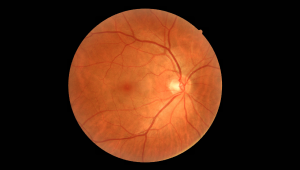

Високоякісне зображення сітківки

Завдяки високій роздільній здатності 12 мільйонів пікселів NFC-700 надає діагностиці сітківки ока та системам AI більш точну та корисну інформацію, що підвищує точність та ефективність діагностики.

| Кут огляду | >=45 градусів | |